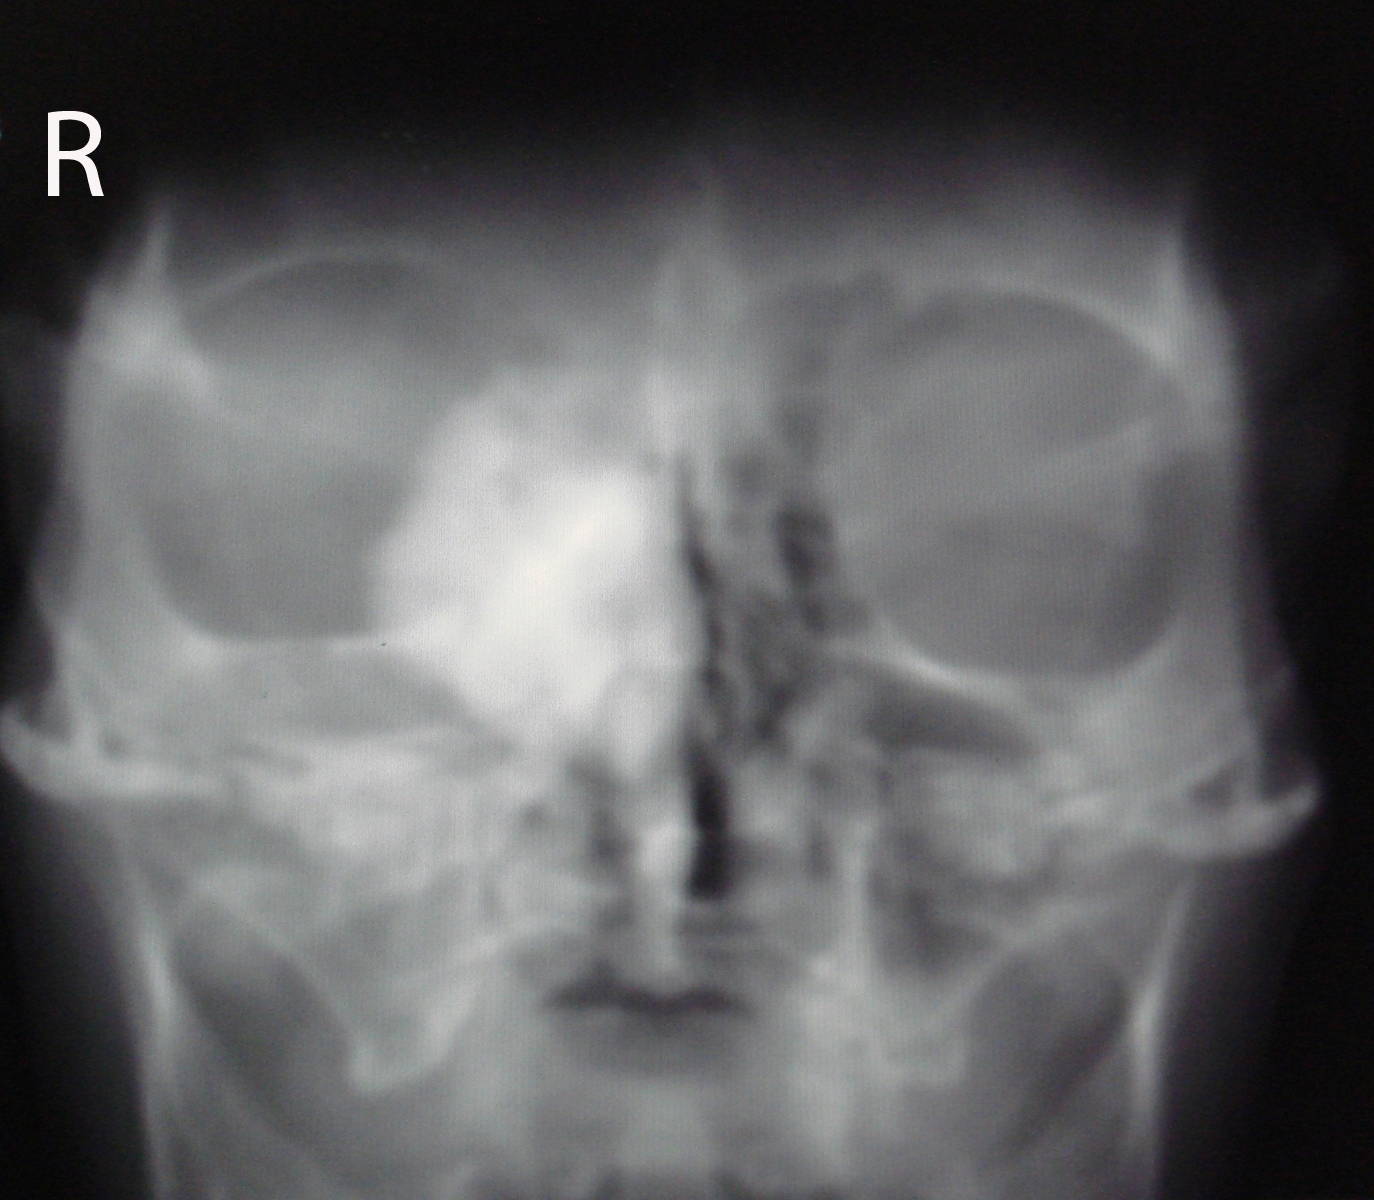

Osteoma is the most frequent benign tumor of paranasal sinuses. Usually osteomas are asymptomatic and discovered incidentally during radiological imaging for other reasons. A giant osteoma with intraorbital extension is rare. Plain radiograph may be useful; however CT scan is the best modality of investigation for diagnosing and treatment planning. In asymptomatic osteomas, serial follow-up can be done. Surgery is performed in the presence of symptoms and signs. We report a case of 60 years old woman with a large osteoma of right ethmoid sinus extending into the ipsilateral orbital cavity.